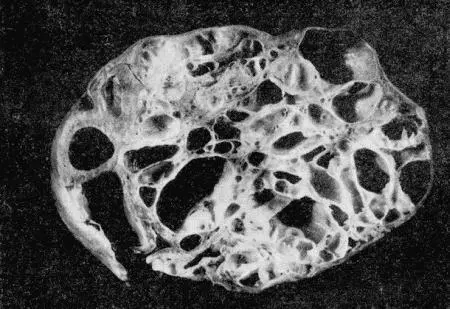

Рис. 156. Саркома матки суки

Опухоли обычно имеют вид единичных, ограниченных шаровидных образований и могут достигать больших размеров. Диффузно растущие опухоли у сук встречаются очень редко. Почти во всех случаях в опухолях обнаруживают кистевидные полости (рис. 156–157). Эти полости представляют собой результат дистрофических процессов, развивающихся в ткани опухоли. Наиболее часто образуется некроз и распад тканей в круглоклеточных и особенно в полиморфноклеточных саркомах. В результате некроза, связанного с жировой дистрофией и ядерным распадом, и образуются кистевидные полости. Причиной некроза может быть кровяной стаз и тромбозы сосудов.

Рис 157 Фибросаркома матки Симптомы опухолей матки зависят от особенностей - фото 160

Рис. 157. Фибросаркома матки